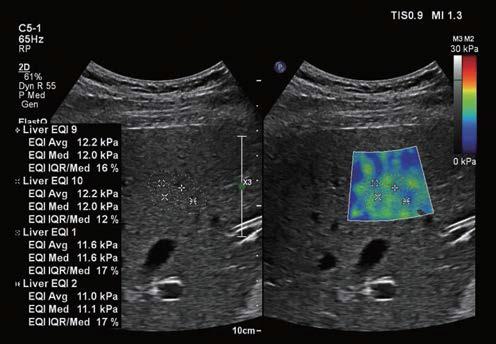

フィリップス、「Liver Fat Quantification(肝脂肪化定量評価。肝臓がん|消化器|診療内容|医療法人 甘木第一クリニック。肝臓がん|消化器|診療内容|医療法人 甘木第一クリニック。sakuraさん専用 蔵王吊るし柿4kg 紅干し柿 600g。Contrast Enhanced Ultrasound (CEUS) | フィリップスヘルスケア。Liver Ultrasonography | SpringerLink。キヤノンメディカルシステムズ、『肝臓の脂肪量の汎用超音波画像。Imaging Features of Hepatocellular Carcinoma in the Non。Imaging Features of Hepatocellular Carcinoma in the Non。714cFtk9QyL._AC_UF350,。肝臓病変における超音波の最新情報-第24回腹部放射線研究会。KMS_M01_XXX_670.jpg。腹部の超音波検査健康なヒト胆嚢 - 胆嚢のストックフォトや画像。